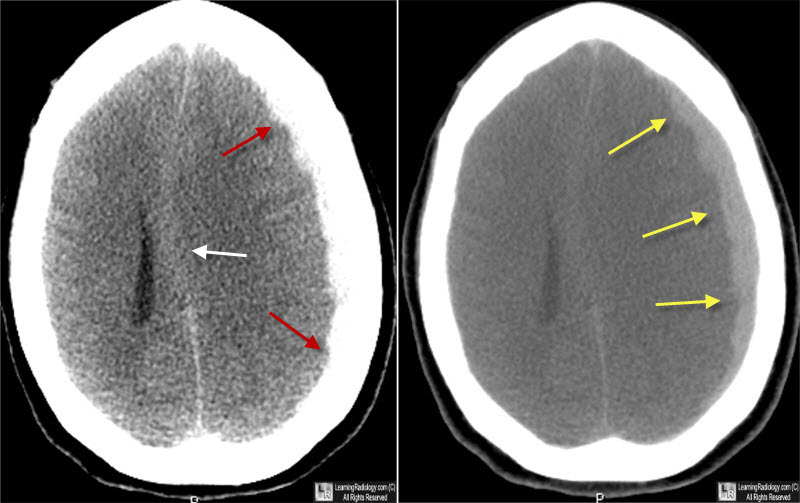

Encontramos una variación sustancial entre centros en el empleo de la craniectomía descompresiva (CD) versus craneotomía para el hematoma subdural agudo traumático. Esta variación en la estrategia de tratamiento no resultó en un resultado funcional diferente. Estos hallazgos sugieren que la CD primaria debe restringirse a pacientes recuperables en los que no es posible el reemplazo inmediato del colgajo óseo debido a la inflamación cerebral intraoperatoria. eClinicalMedicine, 9 de agosto de 2023.